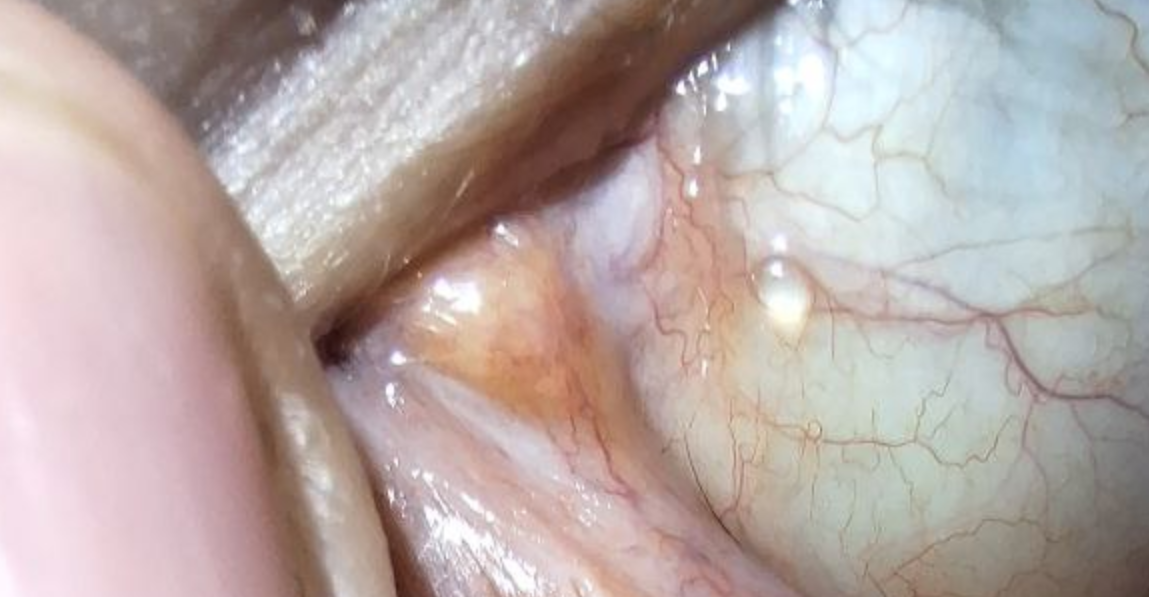

Раньше мог сидеть сутками за компом и все было ок, сейчас 30 минут (не преукрашиваю) и глаза превращаются в пикрил. Ходил к офтальмологам, мне сказали, что с глазами все ок, а от красных глаз покапай увлажняющие куапельки. Только я их и до этого капал.

Кто встречался с таким? Чо за хуйня?

Сейм хуйня, тоже сказали норм, прокапай капельки, только проблема никуда не делась, так еще и сами белки глаз теперь перманентно покрыты красными сосудами.